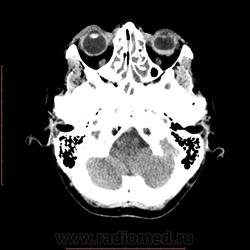

КТ орбит. Образование левого глазного яблока

Женщина 57 лет обратилась с жалобами на снижение зрения левого глаза. На УЗИ объемное образование левого глаза. Написал DDs меланома, ретинобластома.